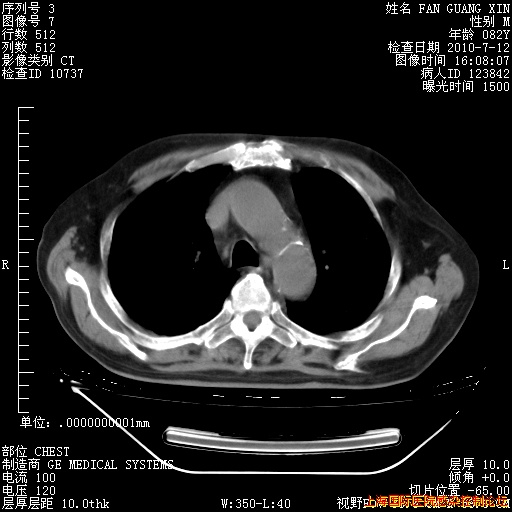

6月12日纵膈窗